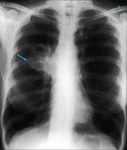

Chest x-ray showing left hilar carcinoma (arrow)

From: E. Dick, Student BMJ. 2000;8:358-360